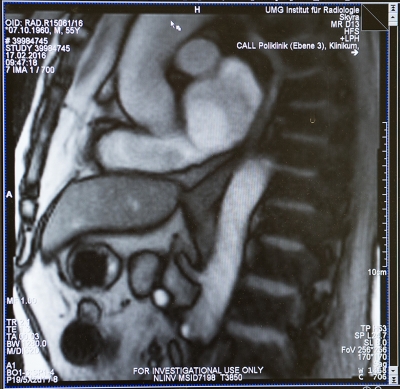

Das Göttinger Forscherteam nutzt dafür das Verfahren der Magnetresonanz-Tomografie (MRT) in Echtzeit. Mit Hilfe dieser Technik, der sogenannten „Echtzeit-MRT“, kann der Schluckakt mit 25 Bildern pro Sekunde dokumentiert und untersucht werden. Das Echtzeit-MRT liefert Bilder, die für diagnostische Zwecke in der Klinik und für die Behandlung nutzbar sind. Ursachen von Sodbrennen oder Schluckstörungen lassen sich genauer erkennen und untersuchen. Für eine individuelle und gezielte Behandlung der Volkskrankheit Sodbrennen eröffnen sich damit neue Wege.

Die Echtzeit-MRT liefert Bilder, mit denen der Schluckvorgang vom Mundraum durch die Speiseröhre bis zum Mageneingang verfolgt werden kann. Auch der Reflux, der entscheidende Akt für Sodbrennen, lässt sich unmittelbar beobachten: Um den Eintritt von Magensäure in die Speiseröhre auszulösen, reicht eine einfache Pressung auf den Bauch des Patienten. „Auf diese Weise lässt sich Sodbrennen diagnostizieren. Gleichzeitig können wir auch die anatomische oder funktionelle Veränderung entdecken, die dem Sodbrennen zugrunde liegt. Wir können jetzt ganz genau sehen, was die Ursache ist: Das kann eine verzögerte Muskelbeweglichkeit (Peristaltik) der Speiseröhre sein oder eine Störung des Übergangs von der Speiseröhre in den Magen oder eine Entleerungsstörung des Magens in den Darm“, so Priv.-Doz. Dr. Beham.